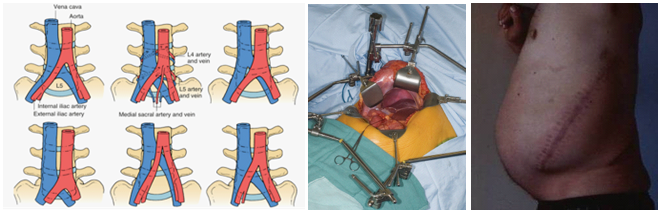

然而,采用传统开放手术的一些弊端逐渐浮现,如腹壁不对称、切口疝、不美观;牵开复杂的大血管时易损伤(1-24%);上腹下丛损伤-逆向射精(4%);附加后路内固定增加手术创伤和费用,影响了人们对开展该技术的热情[9]。

正是由于以上问题,使得人们在开展该技术上存有疑虑并限制了发展,并被打上了“昙花一现”的标签。因此,在1997年,Mayer提出了小切口经肌间、腰大肌-血管自然间隙入路进行腰椎前路手术的新理念[12]。该技术在L2-S1均可采用,L4/5以上腹外侧入路,L5/S1采用下腹入路,手术创伤较传统入路明显减少,但仍然避免不了腹部大血管损伤的问题。

但是,由于D/XLIF技术是采用经腰大肌入路,一些入路固有并发症则无法避免,如腰大肌血肿,腰丛神经损伤(运动障碍 0.7–33.6%,感觉障碍 0–75%);L5/S1受髂骨阻挡,神经电生理检测假阴性,只能通过撑开椎间隙获得间接减压,以及有时需附加钢板或后路手术等问题经常困扰术者[14]。为减少上述问题,OLIF技术应运而生。2012年,Silvestre提出了OLIF(Oblique Lumbar Interbody Fusion),其优势在于:腰大肌外操作,避免血肿及腰丛损伤;植入物倾斜放入,不需过度牵拉血管;植骨块大、椎间高度和前凸恢复好[15]。其不足包括:肋弓(L1-3)和髂骨(L5/S1)阻挡;向前牵拉交感神经—损伤可能;只能获得间接减压;需附加后路手术。